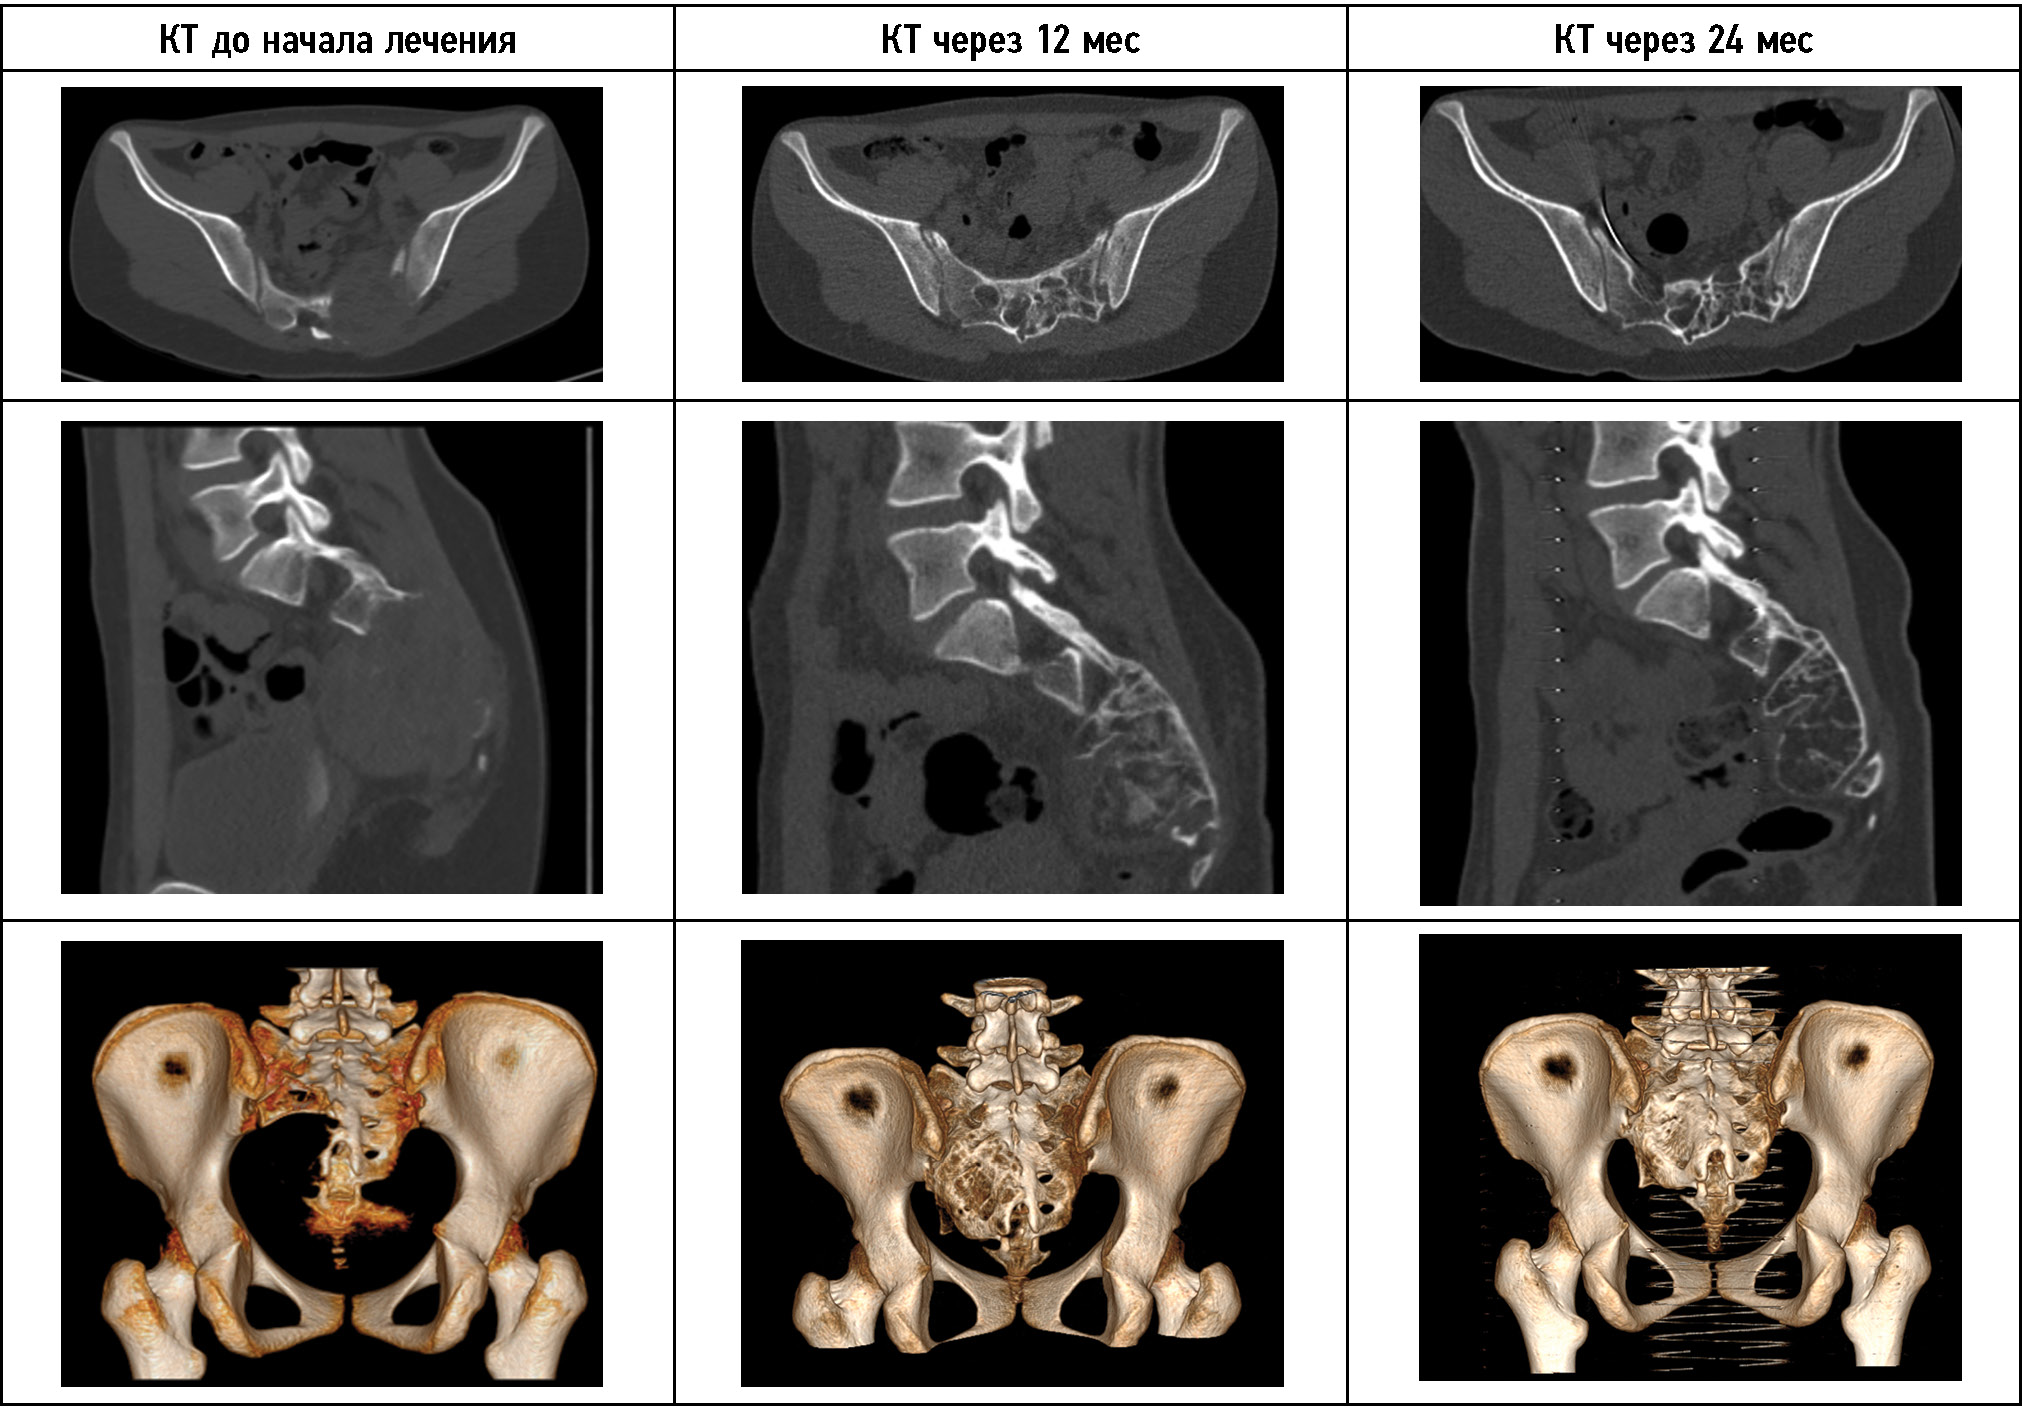

Рис. 3. КТ-динамика лечения пациента 1. На представленных КТ-снимках можно наблюдать уменьшение объёмов кисты, формирование собственной костной ткани. КТ-исследование через 12 месяцев выполнено перед открытой операцией в объёме частичной резекции задней стенки опухоли и дренирования глубоких отделов аневризмальной костной кисты.

Fig. 3. The CT scans of the patient’s treatment show a decrease in the cyst volume and the formation of bone tissue. A follow-up CT scan was done 12 months before the open surgery to partially remove the posterior wall of the tumor and drain the deep sections of the aneurysmal bone cyst.

На момент первой госпитализации возраст пациента составлял 16 лет. По месту жительства выявлено новообразование крестца, выполнена открытая биопсия, гистологически поставлен диагноз — аневризмальная костная киста крестца. При первом поступлении в отделение детской костной патологии и подростковой ортопедии предъявлял жалобы на боль в области крестца до 7 баллов по ВАШ, боль иррадиировала в правую нижнюю конечность до пятки, также отмечал периодическую боль при акте дефекации, запоры. Вышеуказанные жалобы беспокоили с ноября 2021 г. с постепенным ухудшением. Представлены МРТ пациента при первом поступлении в стационар (рис. 2). По данным лучевых методов исследования отмечаются лизис костной ткани в области опухоли, компрессия невральных структур, отдавливание тазовых органов. Оболочка опухоли представлена её мягкотканным компонентом без признаков окостенения. Пункционное лечение начато в апреле 2020 г. При первичной пункции давление в опухоли составило 510 мм вод. ст., кровопотеря — 150 мл. На момент третьей госпитализации (после 4 пункций и 3 месяцев с начала лечения) жалобы на боль и неврологическая симптоматика регрессировали. Можно наблюдать признаки частичной оссификации оболочек опухоли, выстраивание костных мостиков в полости кисты через один год (после 12 пункций) с начала лечения пациента. На 13-й пункции давление менее 120 мм вод. ст., кровопотеря менее 50 мл. В связи со снижением активности принято решение о частичной резекции задней стенки опухоли и дренировании глубоких отделов АКК. Через 6 месяцев введён костнопластический материал Коллап-Ан в полость кисты. На КТ-исследовании через один год после открытой частичной резекции задней стенки опухоли и дренирования глубоких отделов АКК и через 6 месяцев после пункционного введения костнопластического материала определяется постепенное восстановление костной ткани крестца, полное окостенение оболочек кисты. Как и в большинстве случаев при восстановлении костных структур, отмечается формирование просвета позвоночного канала и анатомии крестцовых отверстий по принципам памяти костной формы, что отчётливо визуализируется на контрольных КТ-исследованиях. При динамическом наблюдении и на момент повторных госпитализаций пациент отмечал полный регресс болевого синдрома и неврологической симптоматики уже после четвёртой манипуляции. Данных о продолженном росте патологического процесса получено не было. Пациент проходит этапное пункционное лечение. Динамика КТ-исследования пациента 1 представлена на рис. 3.